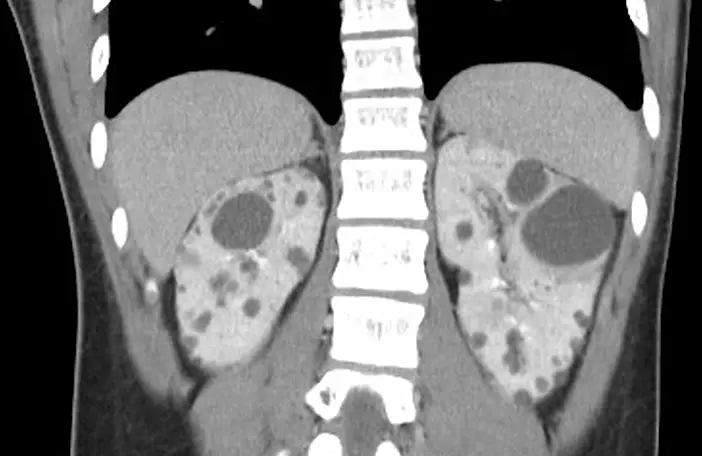

14 歲男童,其父親患有高血壓;男童電腦斷層掃描檢查如圖,其最可能診斷為何? 圖片

圖片為腹部電腦斷層掃描冠狀切面(coronal CT),顯示:

• 雙側腎臟明顯增大,輪廓呈分葉狀(lobulated contour),正常腎臟形態消失

• 雙腎內可見大量多發性囊腫(multiple cysts),大小不等,直徑從數毫米至數公分均有,呈圓形或橢圓形

• 囊腫密度接近水(低密度,CT 值約 0–20 HU),代表內含清澈液體

• 囊腫分布遍及整個腎實質,腎實質受壓、變薄

• 雙側病灶呈對稱性分布,雙腎受累

• 未見明顯腎盂積水、腎結石(高密度鈣化影)或腎臟腫瘤

此影像所見為**多囊腎(polycystic kidney disease)**的典型 CT 表現,結合患者年齡(14 歲)與父親有高血壓的家族史,高度符合 ADPKD。